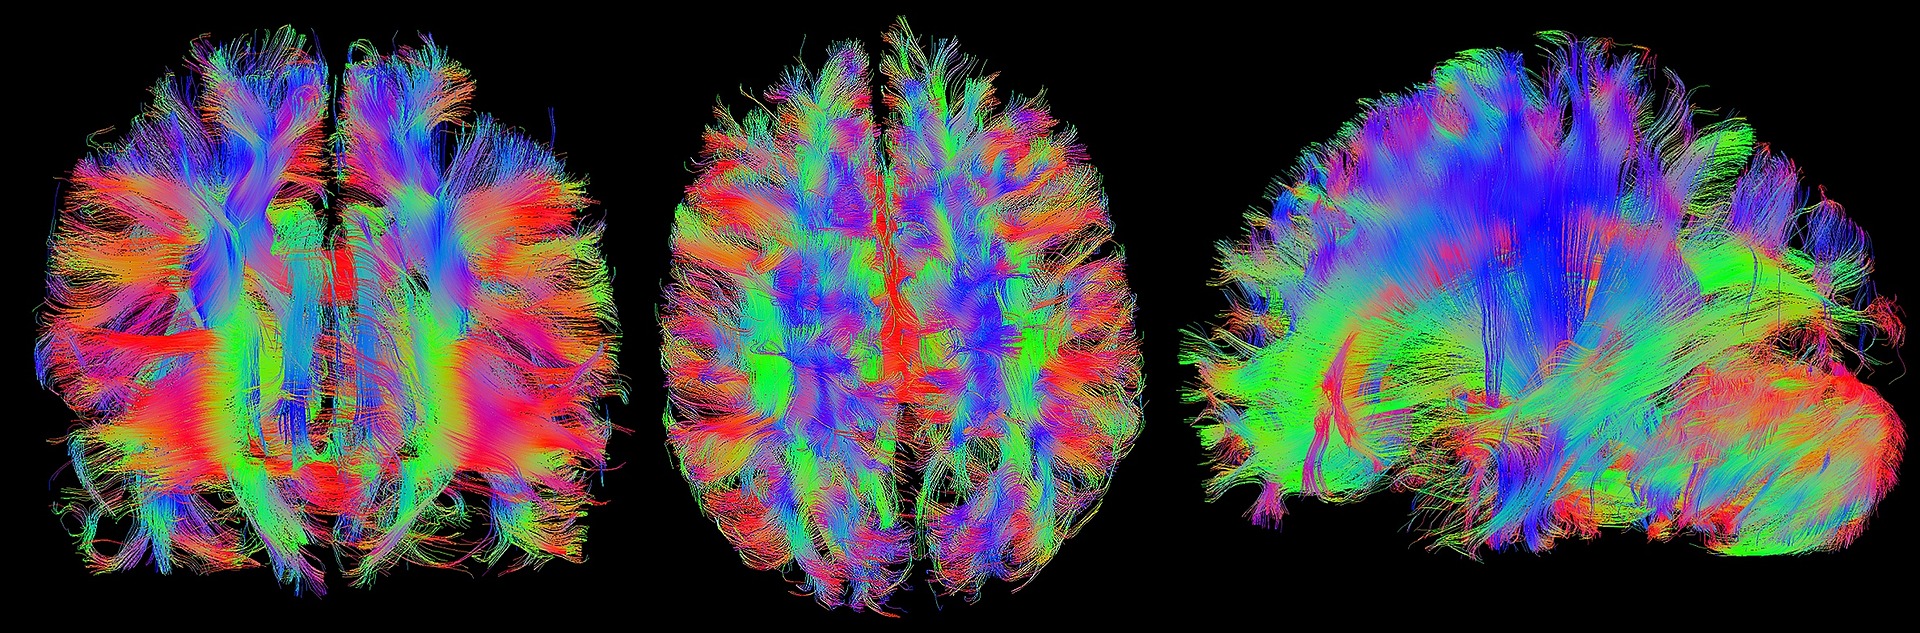

Diffusion tensor imaging (DTI) tractograpy. The color-coding of

Diffusion Tensor Imaging (DTI) revealing connectivity in the brain

Using Diffusion Tensor Imaging (DTI), axonal fiber tractography

A) Diffusion tensor imaging (DTI)-based whole-brain tractogram in